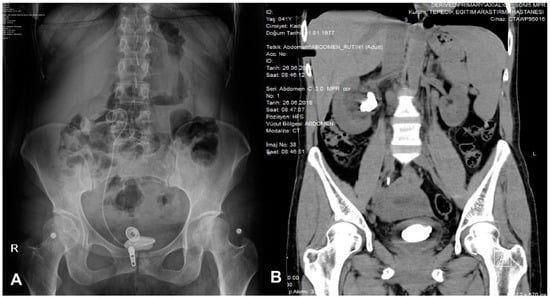

| N | Age/Sex | Side | Reason for Stenting | Indwelling Time (months) | FECal Grade | Fragmentation | Treatment Modality | Operation Time (min) | Hospital Stay (days) |

|---|---|---|---|---|---|---|---|---|---|

| 1 | 50/M | L | Retroperitoneal fibrosis | 15 | III | − | CL + URS | 65 | 1 |

| 2 | 48/M | R | After URS | 8 | IV | − | ESWL + CL | 25 | 1 |

| 3 | 63/F | L | After URS | 12 | III | − | ESWL + URS | 35 | 1 |

| 4 | 55/M | R | Renal transplantation | 60 | III | CL + URS | 50 | 2 | |

| 5 | 41/F | L | Ureteral stone | 8 | III | − | URS | 40 | 1 |

| 6 | 34/F | L | After URS | 15 | V | + | CL + URS + RIRS | 130 | 1 |

| 7 | 32/M | L | After URS | 11 | III | − | CL + URS | 25 | 1 |

| 8 | 23/F | R | Hydronephrosis in pregnancy | 10 | IV | − | CL + RIRS | 100 | 2 |

| 9 | 54/M | R | After URS | 34 | V | − | CL + URS + PCNL | 155 | 3 |

| 10 | 61/M | L | After URS | 16 | III | − | ESWL + URS | 35 | 1 |

| 11 | 59/M | L | Ureteral stone | 9 | III | − | CL + URS | 50 | 2 |

| 12 | 72/F | R | After URS | 28 | V | + | CL + URS + PCNL | 120 | 4 |

| 13 | 68/M | R, L | After URS | 12 | III, III | − | CL + URS | 40 | 1 |

| 14 | 30/F | L | Hydronephrosis in pregnancy | 9 | IV | − | ESWL + CL | 20 | 1 |

| 15 | 33/M | R | After URS | 10 | III | − | CL + URS | 35 | 1 |

| 16 | 58/M | L | Retroperitonel fibrosis | 12 | III | − | ESWL + URS | 25 | 1 |

| 17 | 45/F | R (solitary) | After URS | 10 | III | − | CL + URS | 45 | 1 |